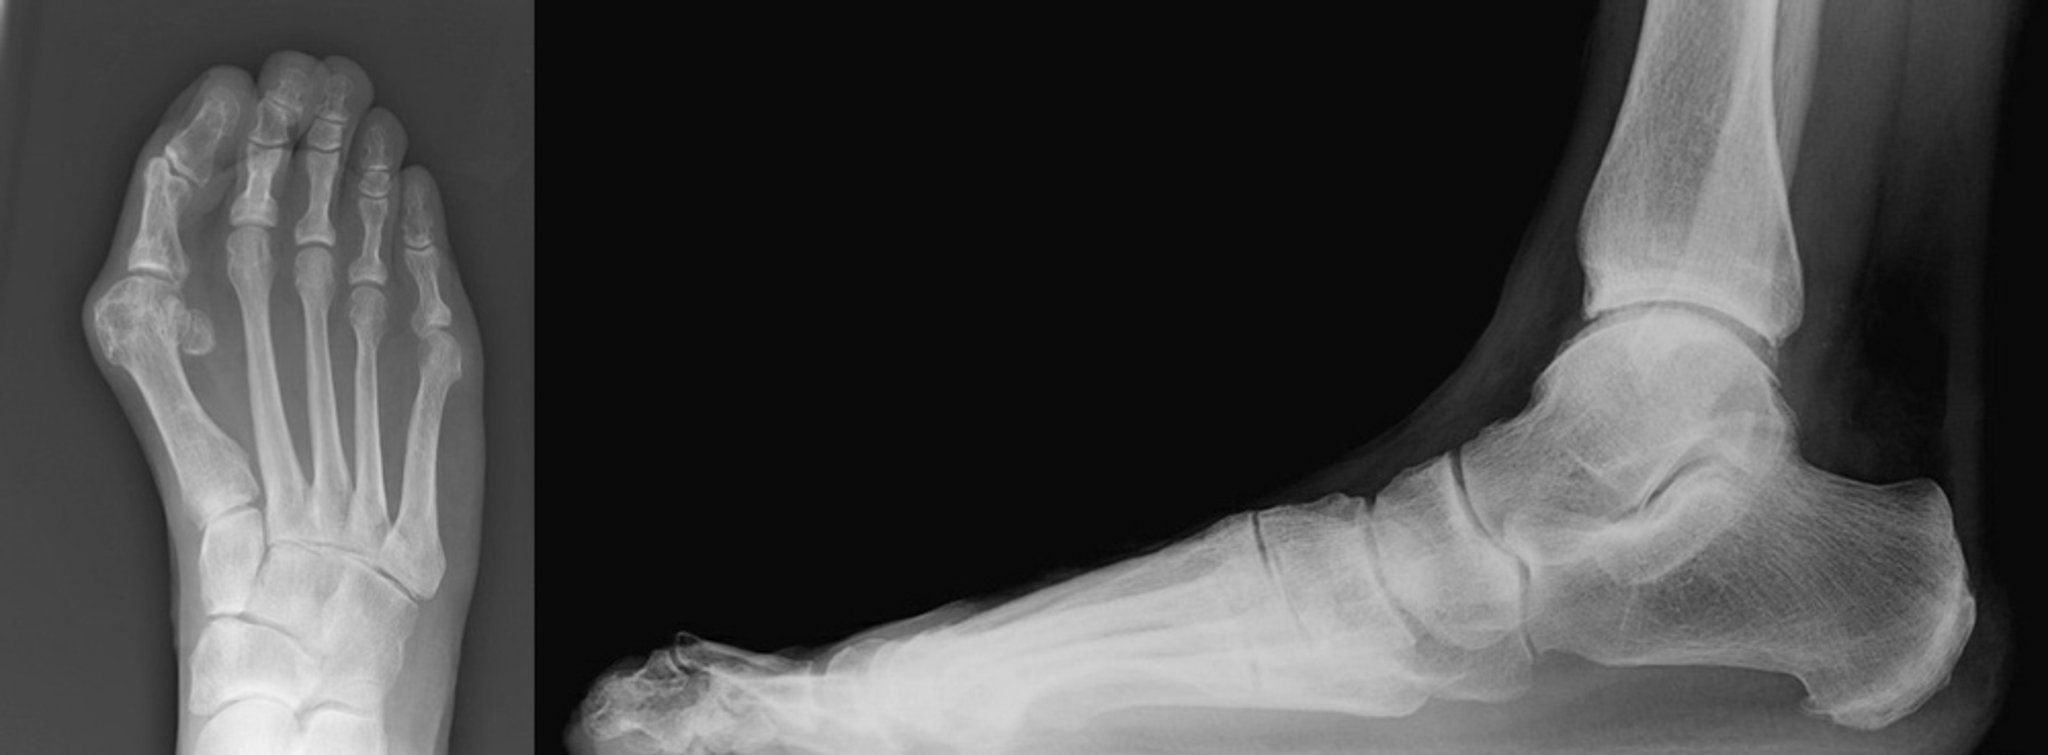

Radiografias de joanete com dedo em martelo

Mostram-se as incidências ântero-posterior e em perfil de um joanete com dedo em martelo do segundo artelho.

A incidência ântero-posterior mostra um hálux valgo grave com desvio medial do primeiro metatarsal. O hálux está pressionando o segundo artelho. O segundo artelho está desviado lateralmente, com estreitamento da segunda articulação metatarsofalângica (à esquerda).

A vista lateral mostra que o segundo pododáctilo está deslocado na articulação metatarsofalângica. Há hiperflexão na articulação interfalângica proximal com hiperextensão da articulação interfalângica distal do segundo pododáctilo (direita).

Imagens cortesia de James C. Connors, DPM.